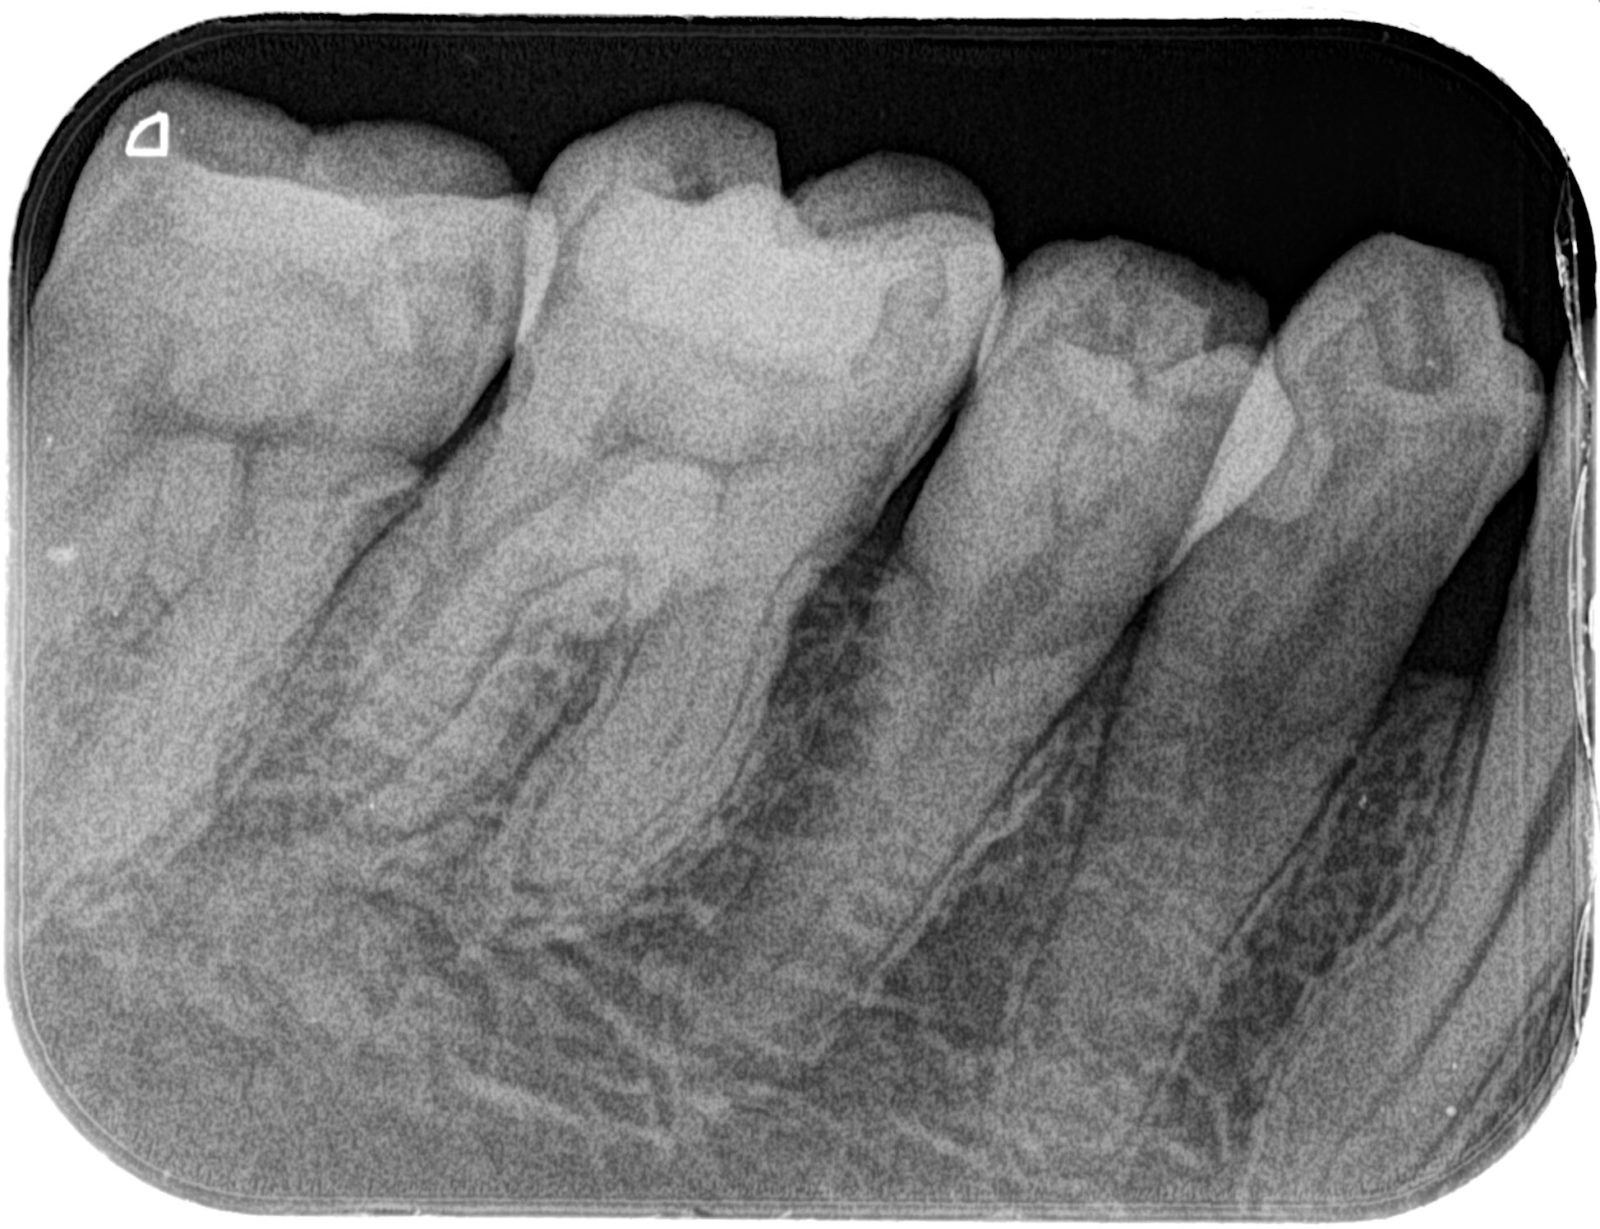

根管治療には「2つ」の治療法があります

根管治療とは、歯の内部にある「歯髄(歯の神経)」や「血管」を治療することを指します。この根管治療の方法は大きく分類すると下記の2つに分けられます。

1 成功率50%前後の「日本式」

2 成功率90%以上の「米国式

です。この成功率の差を生んでいるのは「利用できる材料」「使用できる機材」「治療時間」です。